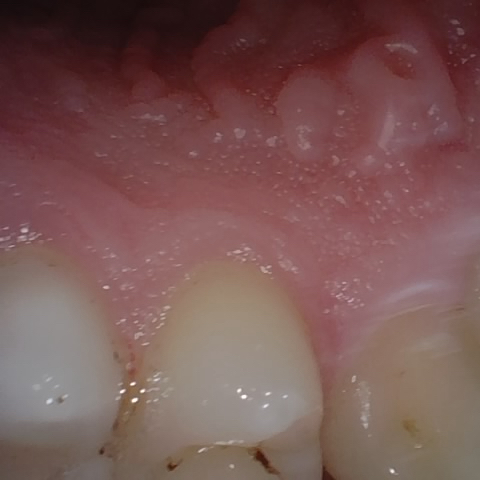

NHD39969

Annotated as "Good"